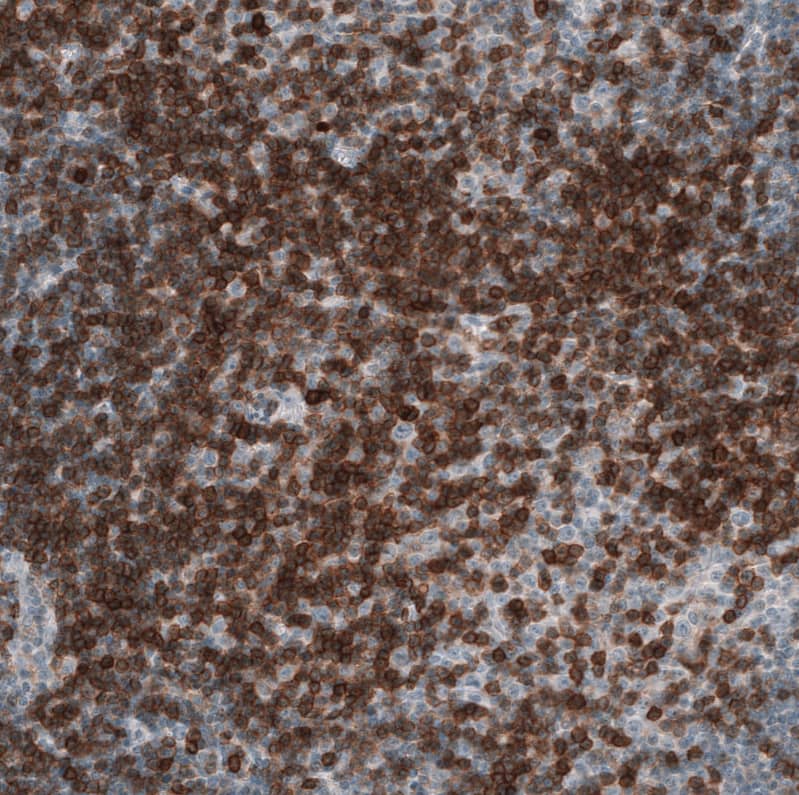

Immunohistochemistry-Paraffin: CD5 Antibody [NBP3-44269]

Staining of human chronic lymphocytic leukemia shows strong membranous positivity in tumor cells.